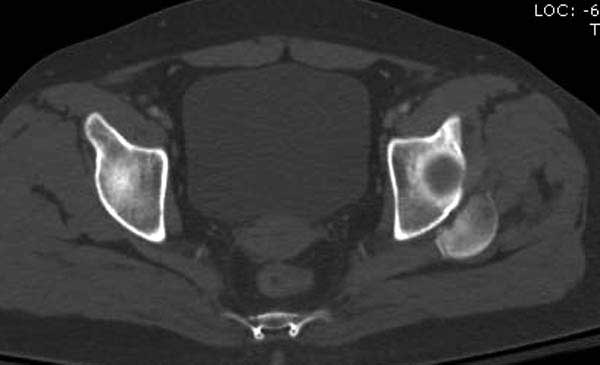

Женщина 28 лет, политравма.

По протоколу обследования больных с травмой сделаны все исследования и выставлен диагноз: разрыв печени и селезенки; множественные переломы ребер и лицевого черепа; стабильный перелом позвоночника, переломо-вывих головки левого бедра, перелом диафиза правого бедра, переломо-вывих правого тарана.

----------- следущая часть -----------

Вложение не в текстовом формате было извлечено&hellip;

Имя     : 8 CT3.JPG

Тип     : image/jpg

Размер  : 26337 байтов

Описание: отсутствует

Url     : http://weborto.net:8080/pipermail/ortho/attachments/20120618/4c283bf6/attachment-0022.jpg